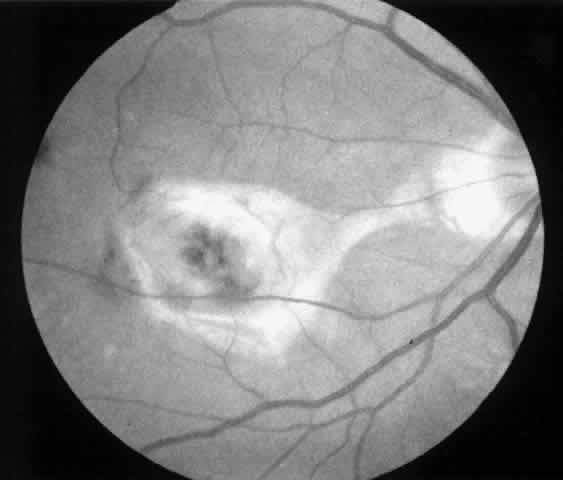

2. A 35-year-old patient developed an idiopathic subfoveal choroidal neovascular membrane with decrease in vision to 20/200 (6/60) (Fig. 9). He underwent surgical excision of the membrane. Laser was applied to the retinotomy at the conclusion of the case. One year after surgery, his visual acuity remained stable at 20/20 (6/6) (Fig. 10).

Fig. 9. Preoperative fundus photograph of a 35-year-old patient with idiopathic subfoveal neovascularization (case 2). Visual acuity is 20/200 (6/60).

Fig. 10. Postoperative fundus photograph (case 2). One year after surgery, visual acuity is 20/20 (6/6). Note laser scar at retinotomy site (arrows).